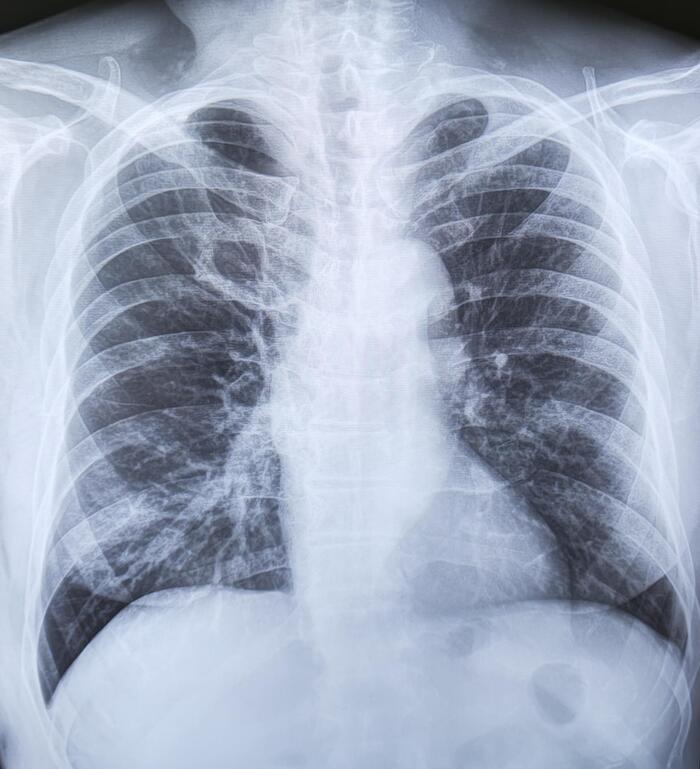

Ребро Люшка

Ребро Люшка - врожденная аномалия развития ребра в виде удвоения его переднего отдела